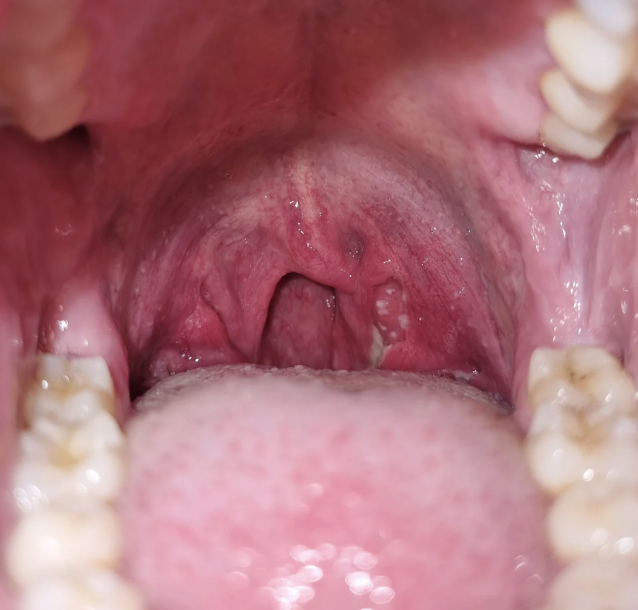

Tonsillitis is the inflammation of the tonsils. Tonsils are two oval-shaped pads of lymphoid tissue located at the back of the throat and form an important part of the immune system. They act as filters by trapping bacteria and viruses that could otherwise enter the airways and cause infection. Tonsils also help the body by producing antibodies to fight infections.

Types of Tonsillitis

Acute Tonsillitis

Sudden inflammation of the tonsils causing severe throat pain, fever, and difficulty swallowing.

Chronic Tonsillitis

Persistent tonsil inflammation leading to repeated sore throats and recurrent tonsil infections.

Recurrent Tonsillitis

Multiple tonsillitis episodes in a year with recurring throat pain and infections.

Peritonsillar Abscess

Collection of pus near the tonsil causing intense pain, swelling, and difficulty opening the mouth.